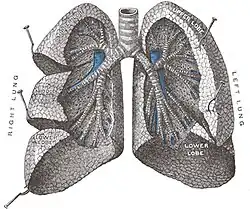

La superficie de los pulmones es de color rosado en los niños y algo más grisácea en los adultos. El peso depende del sexo y del hemitórax que ocupen: el pulmón derecho pesa en promedio 600 gramos y el izquierdo 500 g. Estas cifras son un poco inferiores en el caso de la mujer, debido al menor tamaño de la caja torácica, y algo superiores en el varón.[1] Se describen en ambos pulmones un vértice o ápex correspondiente a su porción superior y una base o porción inferior que se apoya en el músculo diafragma. El pulmón derecho está dividido en 3 lóbulos por dos cisuras, mientras que el izquierdo cuenta únicamente con 2 lóbulos, superior e inferior, separados por una cisura.

Cisuras y lóbulos

El pulmón derecho está dividido por dos cisuras (mayor y menor) en 3 partes o lóbulos (superior, medio e inferior). El pulmón izquierdo tiene dos lóbulos (superior e inferior) separados por una cisura (oblicua). La cisura mayor de ambos pulmones va desde el cuarto espacio intercostal posterior hasta el tercio anterior del hemidiafragma correspondiente. En el pulmón derecho separa los lóbulos superior y medio del lóbulo inferior, mientras que en el pulmón izquierdo separa los dos únicos lóbulos: superior e inferior. La cisura menor separa los lóbulos superior y medio del pulmón derecho y va desde la pared anterior del tórax hasta la cisura mayor. Puede estar ausente o incompleta en hasta un 25 % de las personas.